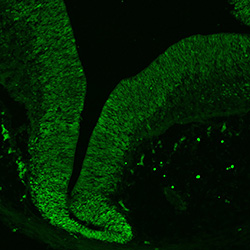

MAP2

11PCW human midbrain